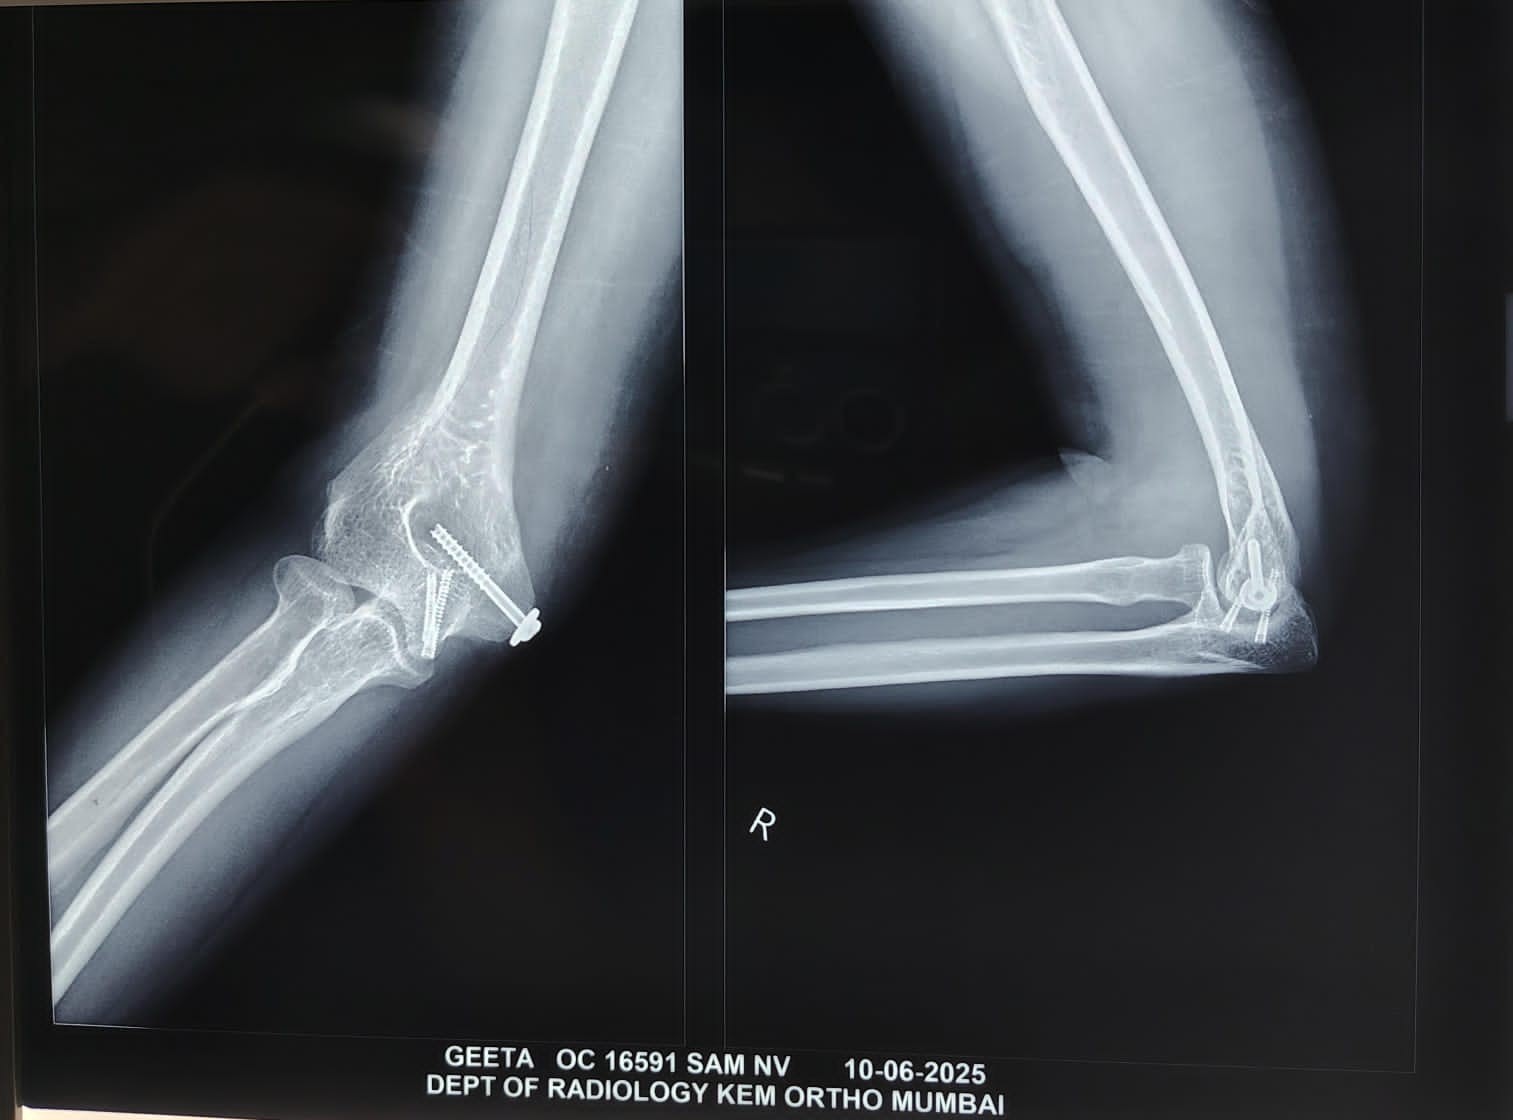

The patient was followed up at week 2, week 6, month 3, and month 6. The range was satisfactory, and the patient achieved a Mayo Elbow performance index score of 91 at 6 months. Plain radiographs at 12 months demonstrate union and articular congruency (Fig. 8).

Figure 8: Radiographs 12 months post-operative showing union and articular congruency.